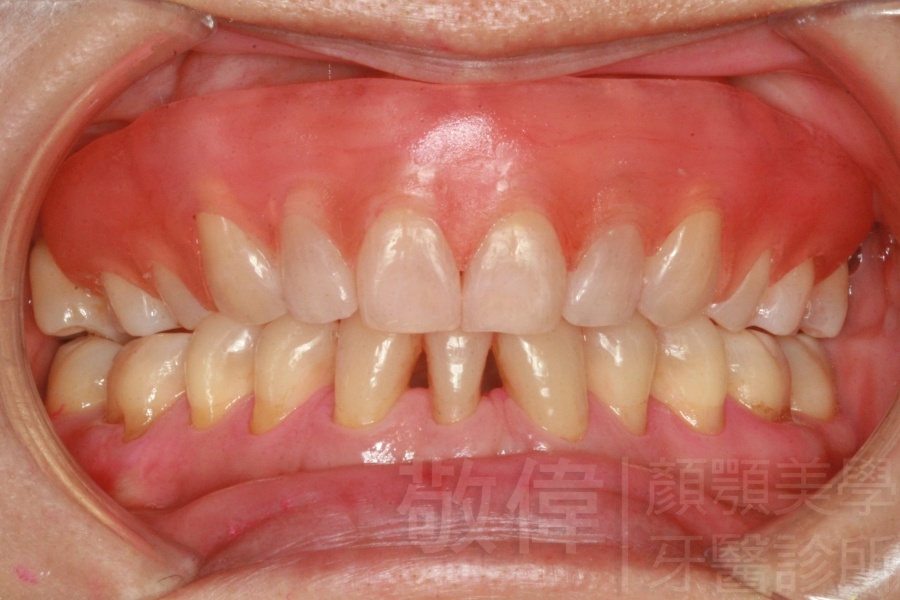

齒顏矯正/上下暴牙嘴唇不容易合起來

矯正前-右   矯正前-正   矯正前-左

矯正前-上   矯正前-下

<個案說明>

上下暴牙嘴唇不容易合起來,經矯正完成後,嘴唇很容易合起來。在學生時期的時候的他,舉止之間充滿著有自信,當時還參加了舞蹈社團,充滿了多采多姿的生活。